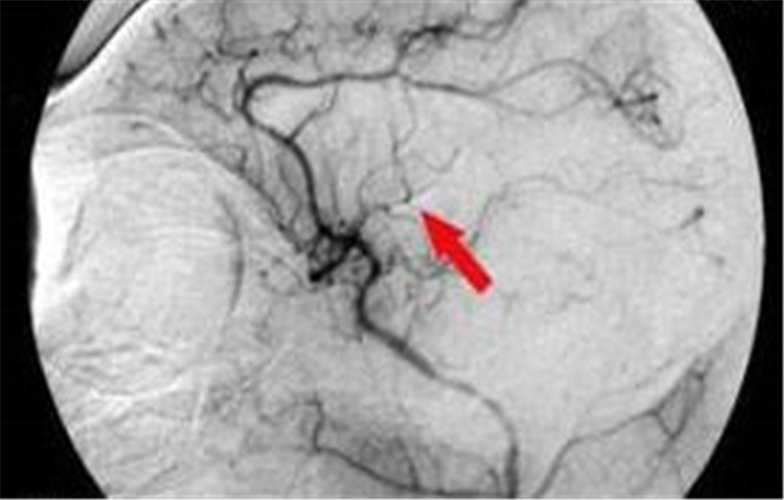

一過性腦供血不足檢查

腦供血不足造影

腦供血不足血管造影